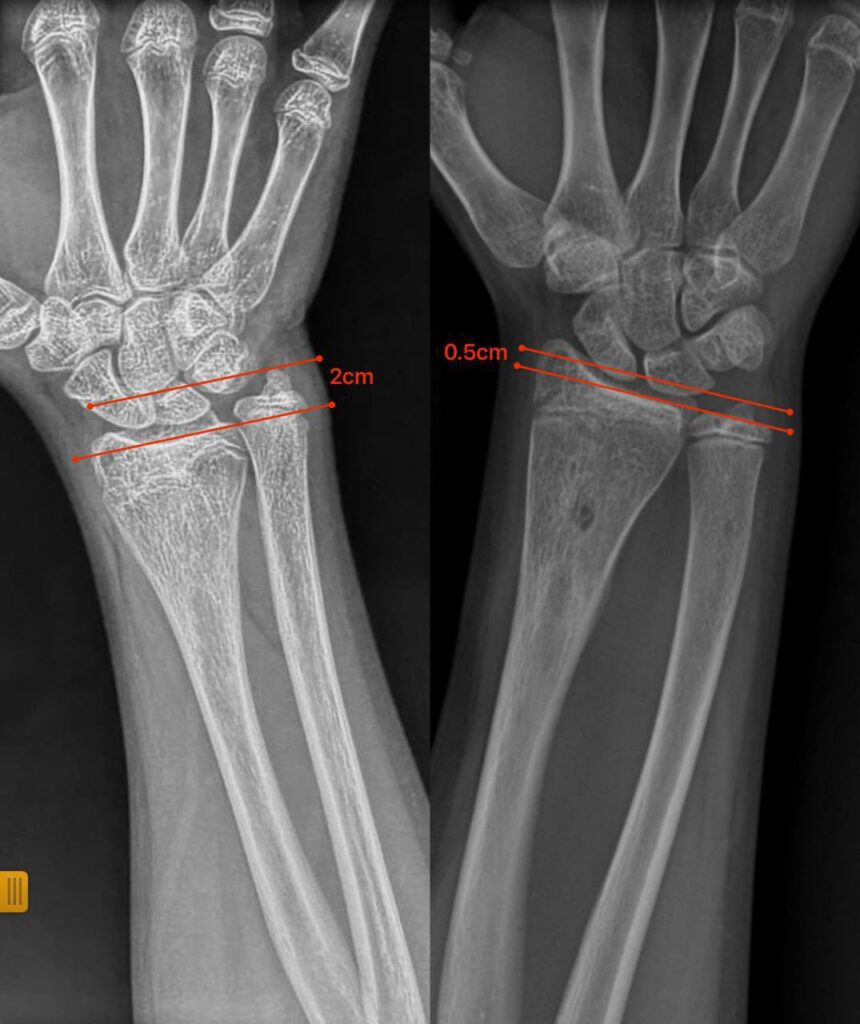

Нещодавно до відділення звернулися батьки 12-річної дівчинки з іншої області з післятравматичною деформацією кісток передпліччя. Лікарі виявили, що ріст кістки порушився через утворення кісткового мостика, який заважав росту кістки та деформував її.

Під час операції спеціалісти видалили кістковий місток під контролем ендоскопа. Такий малотравматичний підхід дозволив відновити природний ріст кістки без складних остеотомій чи встановлення металоконструкцій.

Через сім місяців передпліччя дівчинки повністю відновило форму, ріст кістки нормалізувався, а рухливість кінцівки збережена.

Цей випадок демонструє, що не всі деформації потребують складних оперативних методик: іноді достатньо усунути першопричину порушення росту, щоб кістка розвивалася природним шляхом.